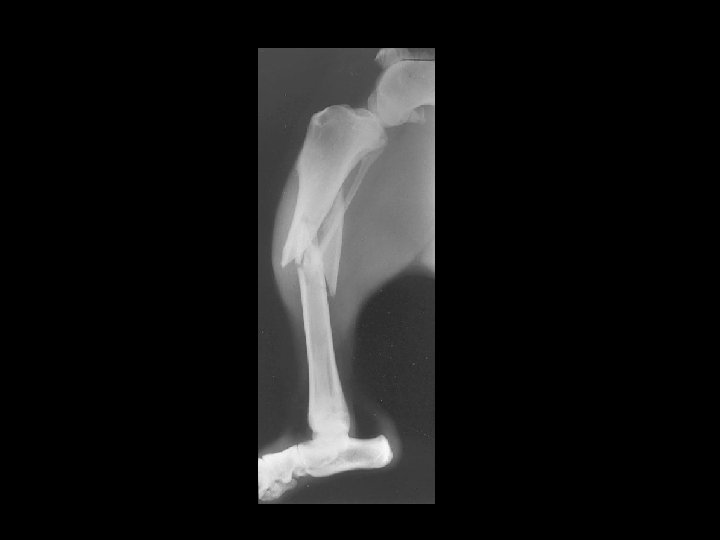

External Fixator

Ilizarov and external fixator